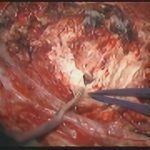

術中写真

摘出 前

摘出 中

摘出 後